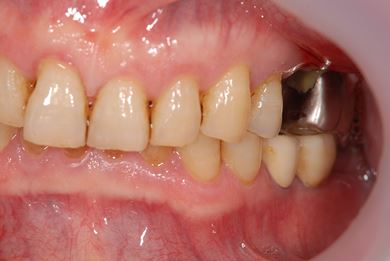

インプラントの症例写真 IMPLANT

抜歯即日スピードインプラント治療

| 治療内容 | インプラント2本(抜歯即日スピードインプラント) | ||||||||||||||||||||||||||||||||